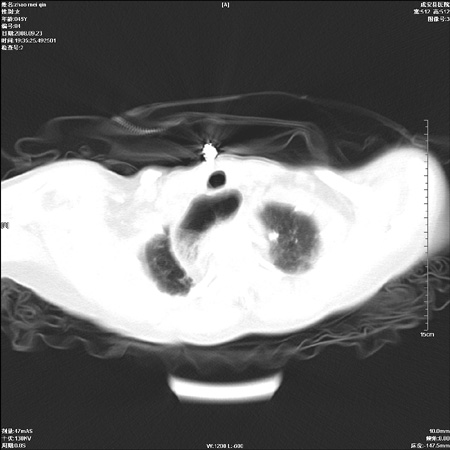

标题: CT15861:女 60 外伤后1小时 胸疼 [打印本页]

标题: CT15861:女 60 外伤后1小时 胸疼

外伤后1小时 胸疼 是外伤后引起的吗?

未除外食道异物。如食道石长时间受阻。

不除外贲门占位梗阻

非外伤性改变,典型的贲门失迟缓症